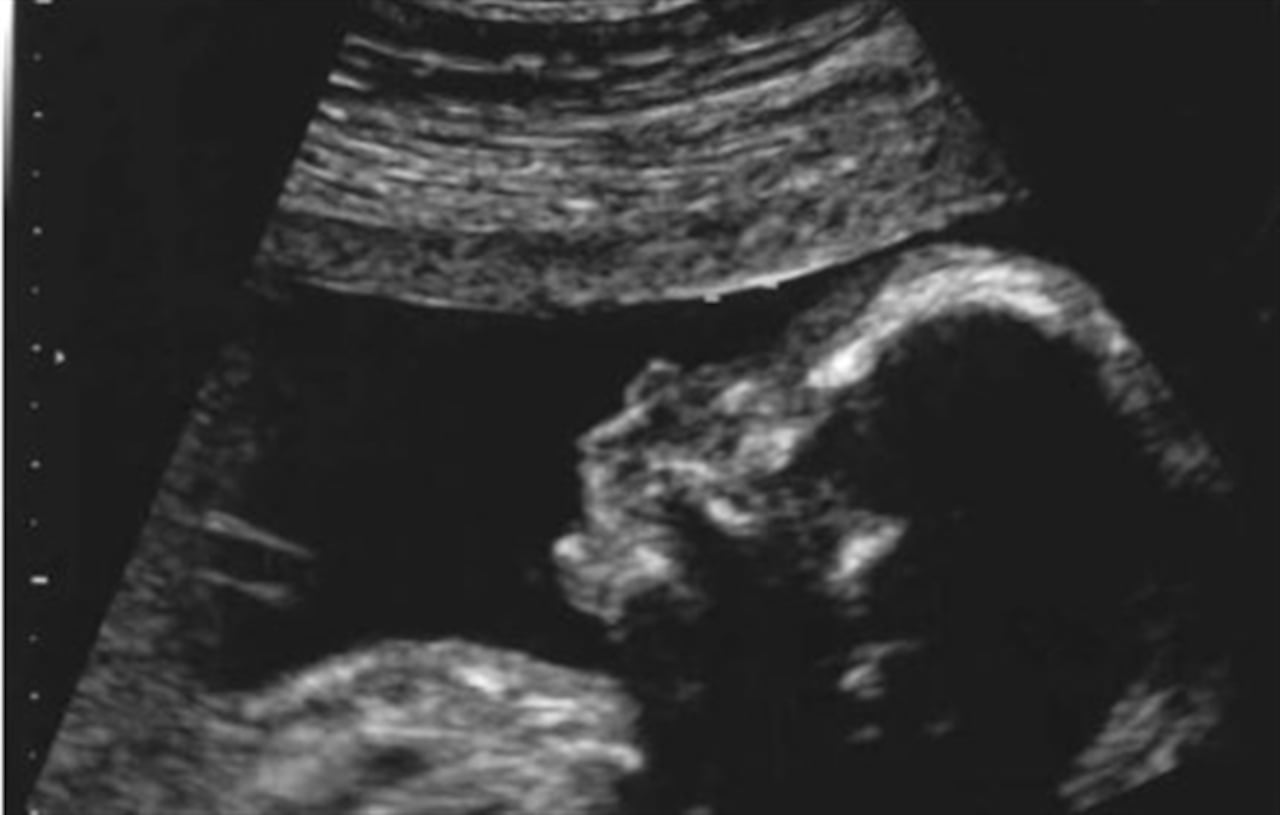

Conocer el sexo de tu bebé y vivir de cerca todas sus etapas de desarrollo es posible a través de la ecografía. No obstante, estas no son las únicas ventajas de practicarte este sencillo examen a tiempo y con regularidad, pues es gracias a él que tu médico puede detectar si tu bebé presenta algún problema o anomalía en su formación.

Cuando te realizan una ecografía, el médico puede visualizar a tu bebé en su ambiente intrauterino a través de ondas de ultrasonido. De esta manera, el especialista evalúa el bienestar y crecimiento de tu hijo en sus diferentes fases de formación, determina el estado de tu embarazo y los cuidados que debes tener.

La primera ecografía se realiza por vía vaginal y debes practicarla tan pronto como sospeches de tu embarazo. De esta manera tu médico podrá evaluar la ubicación del bebé, conocerá el número de fetos, definirá con mayor precisión su edad y evaluará su estado de salud.